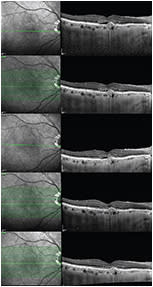

So consider using OCT to evaluate possibly treatment-resistant eyes at visits between injections (one to three weeks) to distinguish between a true nonresponder and one who is responding inadequately. If at this shorter interval we observe resolution of the exudative changes on OCT, we might consider shortening the retreatment interval, rather than switching agents (Figure 2).

Figure 2. How can we differentiate between persistent fluid and a treatment interval that is too late? This sequence of OCT scans provides evidence beyond the appearance of type 1 CNV, with subretinal fluid after three monthly injections of ranibizumab (OCT scan at top). The patient was reinjected, and a follow-up visit was scheduled eight weeks later, observing the presence of subretinal fluid (second OCT scan). After a subsequent intravitreal injection of ranibizumab and a follow-up visit six weeks later, subretinal fluid was also noted (third OCT scan). Thus, another intravitreal injection of ranibizumab was performed, and a new visit was scheduled two weeks later, with complete resolution of subretinal fluid seen (fourth OCT scan). This complete resolution was also seen four weeks after the intravitreal injection (fifth OCT scan), so we considered the correct retreatment interval to be four weeks. This was not a case of nonresponding neovascular AMD; rather, the retreatment schedule had not been properly individualized for this particular case.